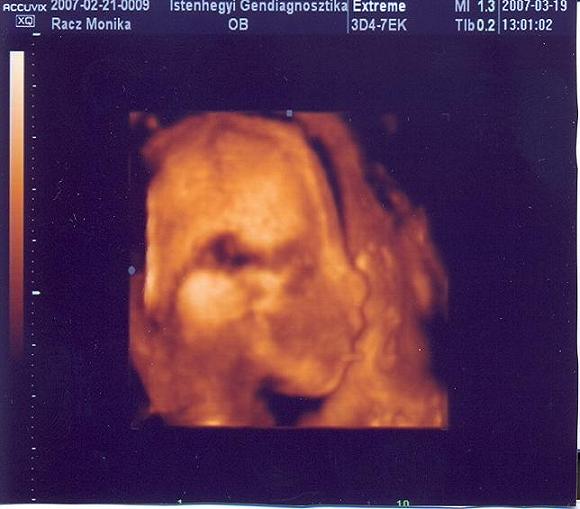

Én sajnos csak a 12. hetén hallottam először, mert a kórházamban az UH-s doki nem mutatta meg. Még a babát sem láttam, csak a párom. Aztán a genetikai tanácsadáson nemcsak láttam, de hallottam is a kis szívét verni.